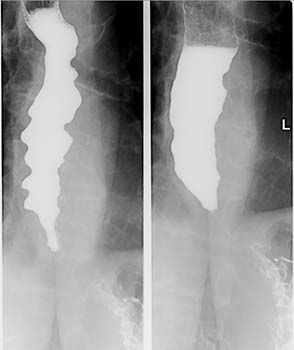

- Barium swallow- This imaging study is done by asking patient to drink a contrast solution which will help visualize the esophagus. Barium swallow shows dilated esophagus, bird beak appearance due to narrowing of distal esophagus.